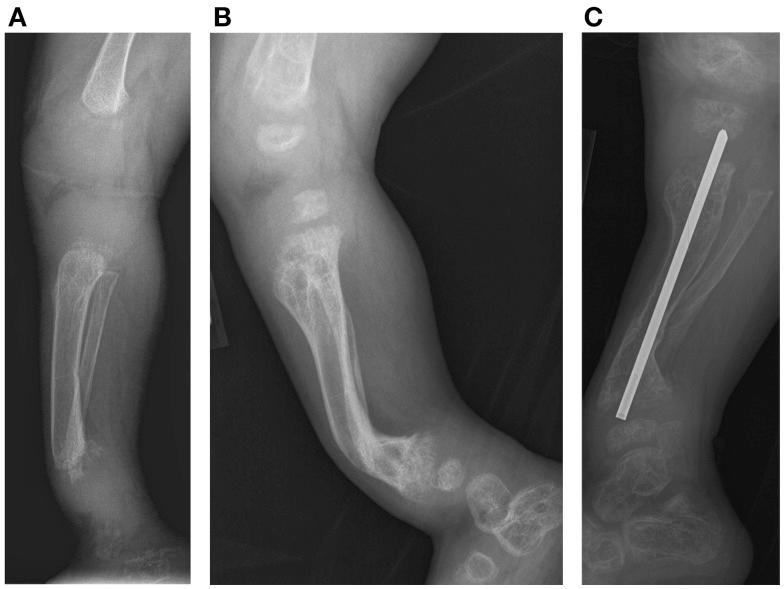

We present two siblings affected with opsismodysplasia (OPS), a rare skeletal dysplasia caused by mutations in the inositol polyphosphate phosphatase-like 1 gene. The skeletal findings include short stature with postnatal onset micromelia, marked platyspondyly, squared metacarpals, delayed skeletal ossification, metaphyseal cupping, and postnatal micromelia. Respiratory compromise, delayed ambulation, and progressive lower extremity deformities are described. The severity of findings is variable. Renal phosphate wasting is associated with severe bone demineralization and a more severe phenotype. This report represents the first described cases of opsismodysplasia treated with intravenous bisphosphonate (pamidronate). Surgical management for lower extremity deformities associated with OPS is also reviewed.

我们介绍了两名受 opsismodysplasia(OPS)影响的兄弟姐妹,这是一种罕见的骨骼发育不良,由肌醇多磷酸磷酸酶样 1 基因突变引起。骨骼表现包括出生后出现的身材矮小、短肢畸形、明显的扁平椎骨、掌骨方形、骨化延迟、干骺端杯状凹陷和出生后短肢畸形。描述了呼吸窘迫、行走延迟和进行性下肢畸形。发现的严重程度是可变的。肾磷酸盐丢失与严重的骨质脱矿和更严重的表型有关。本报告代表了首例接受静脉双膦酸盐(帕米膦酸)治疗的 opsismodysplasia 病例。还回顾了与 OPS 相关的下肢畸形的手术治疗。